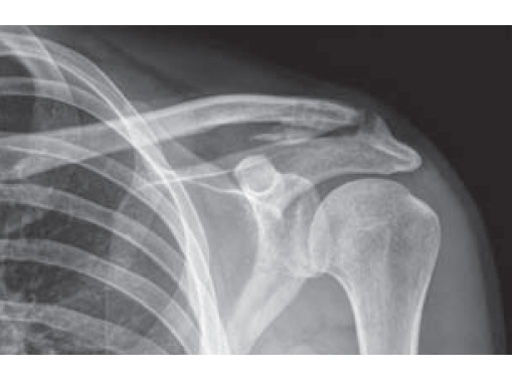

Fig.

Follow-up x-ray after 5 month. Stable AC joint, full function. Persisting ossification in coracoclavicular ligament without clinical relevance.Follow-up x-ray after 10 weeks. Begining ossification in coracoclavicular ligament.